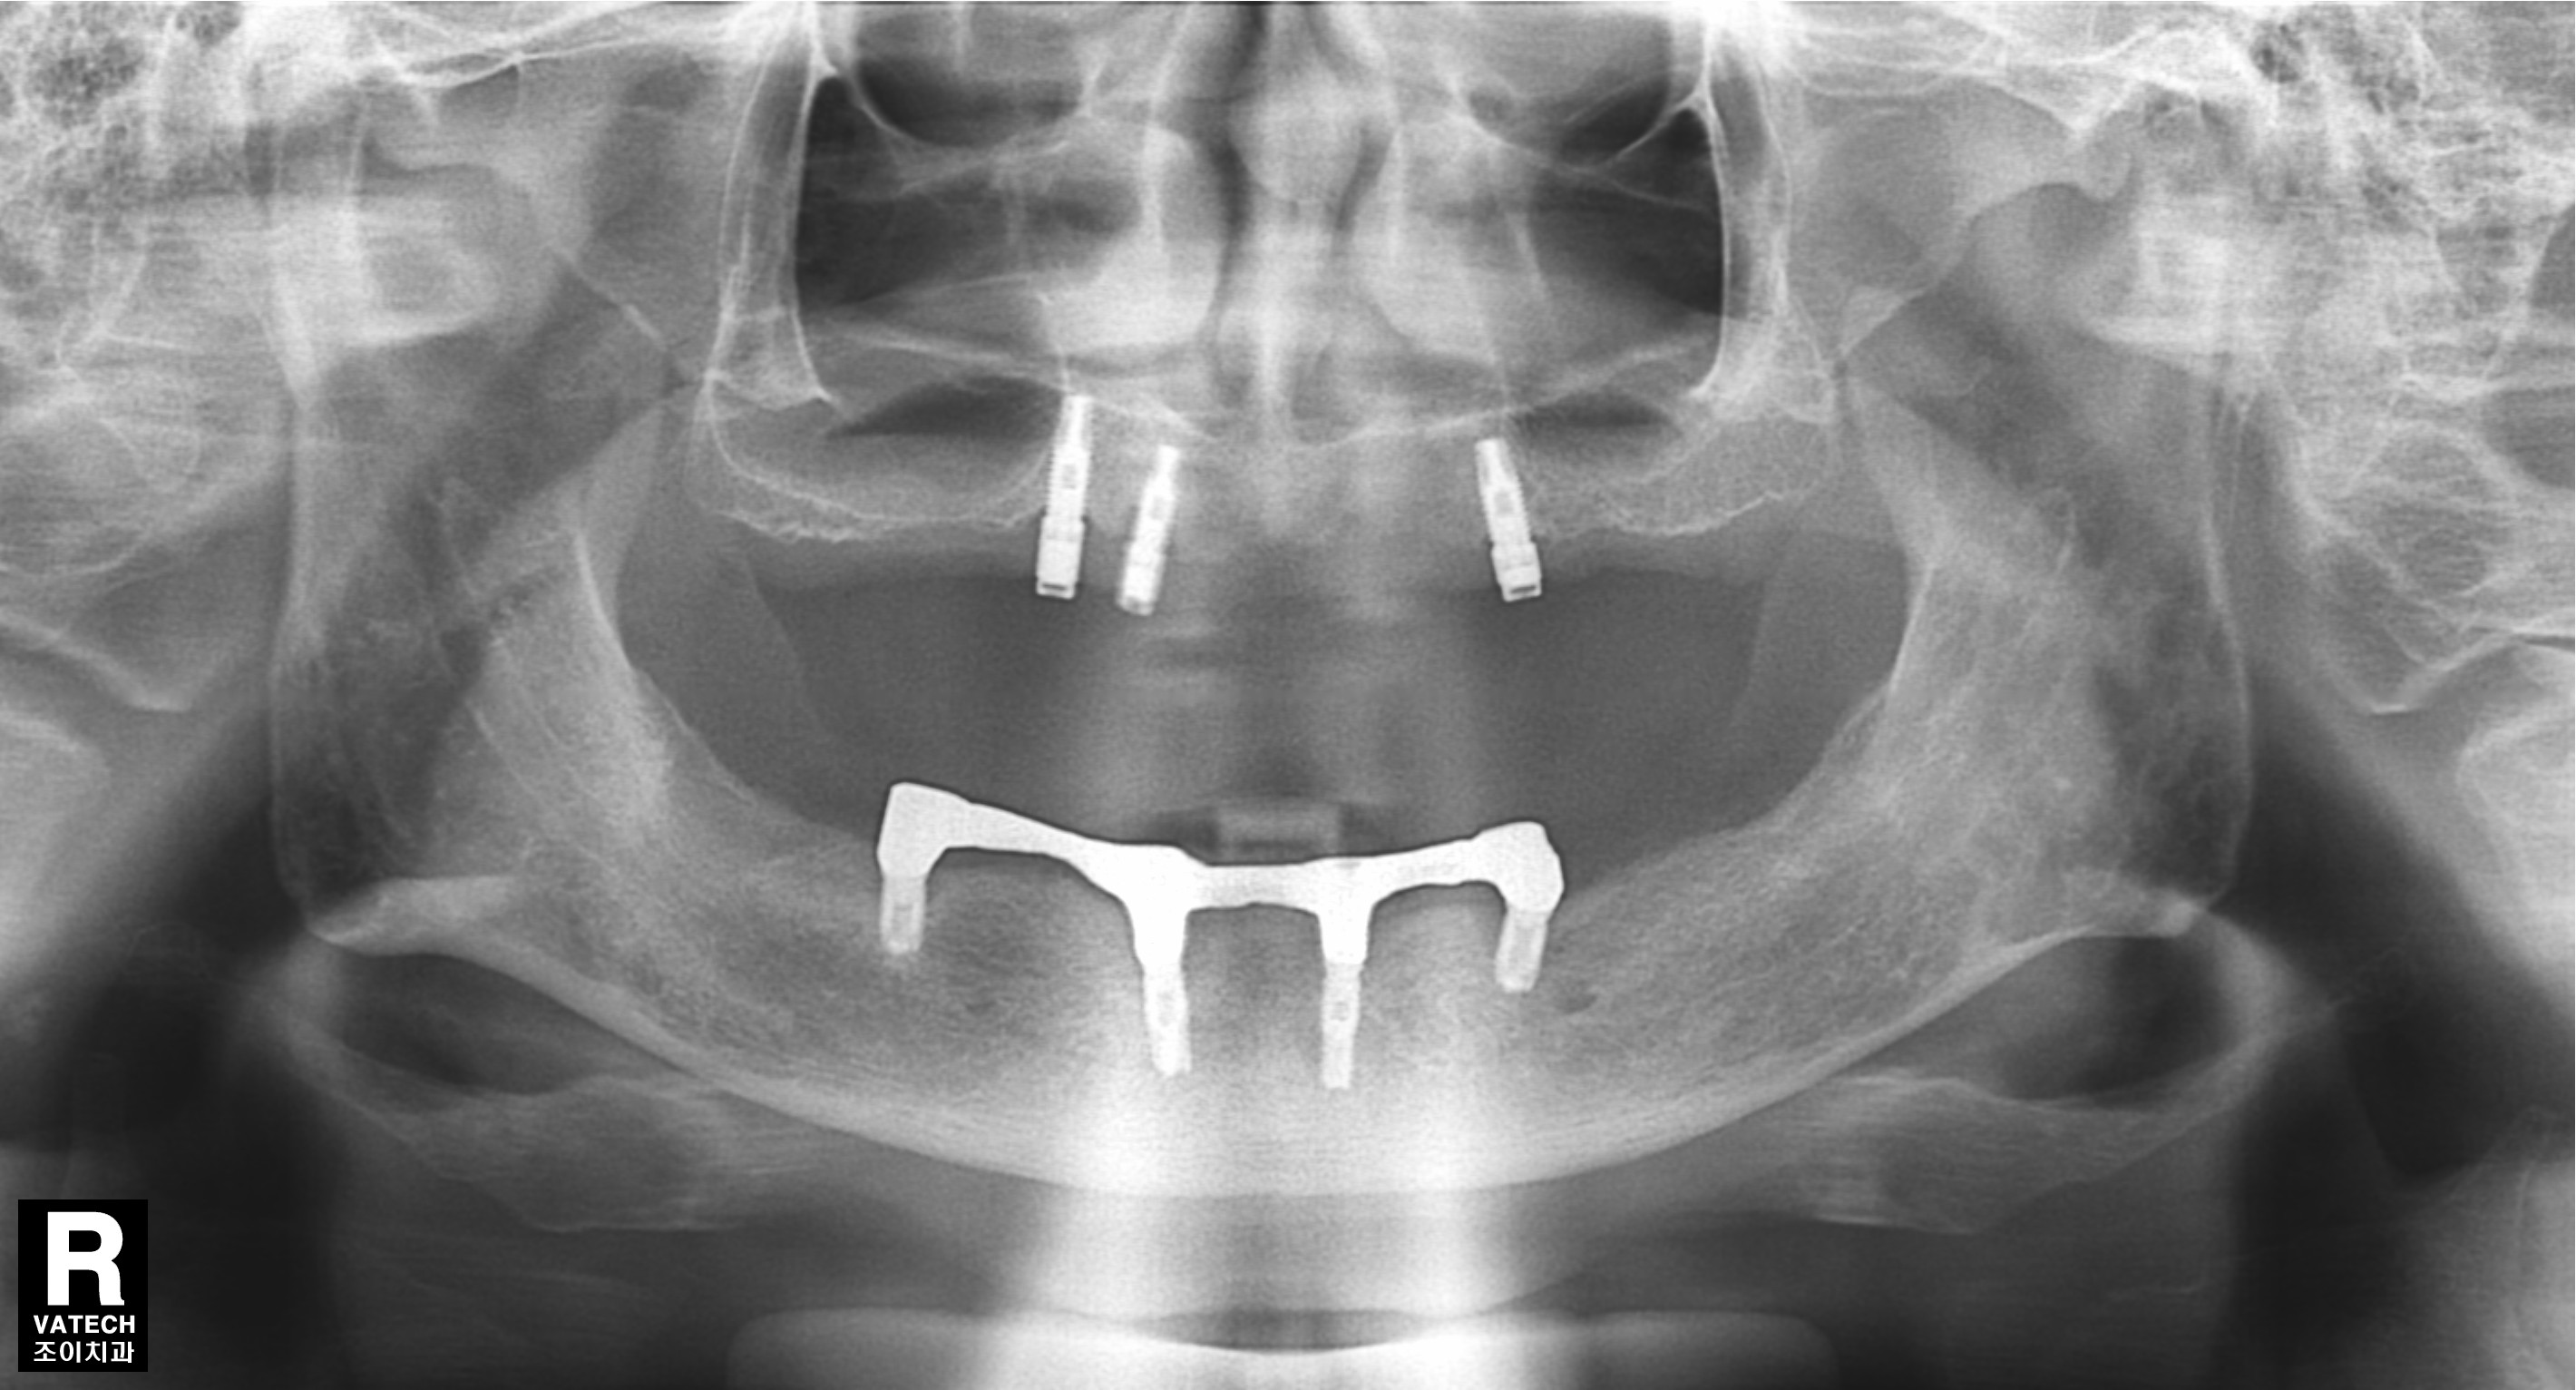

[임플란트] 제목 : 임플란트 지지틀니

상하악 임플란트 지지틀니로 13년째 사용중이십니다.